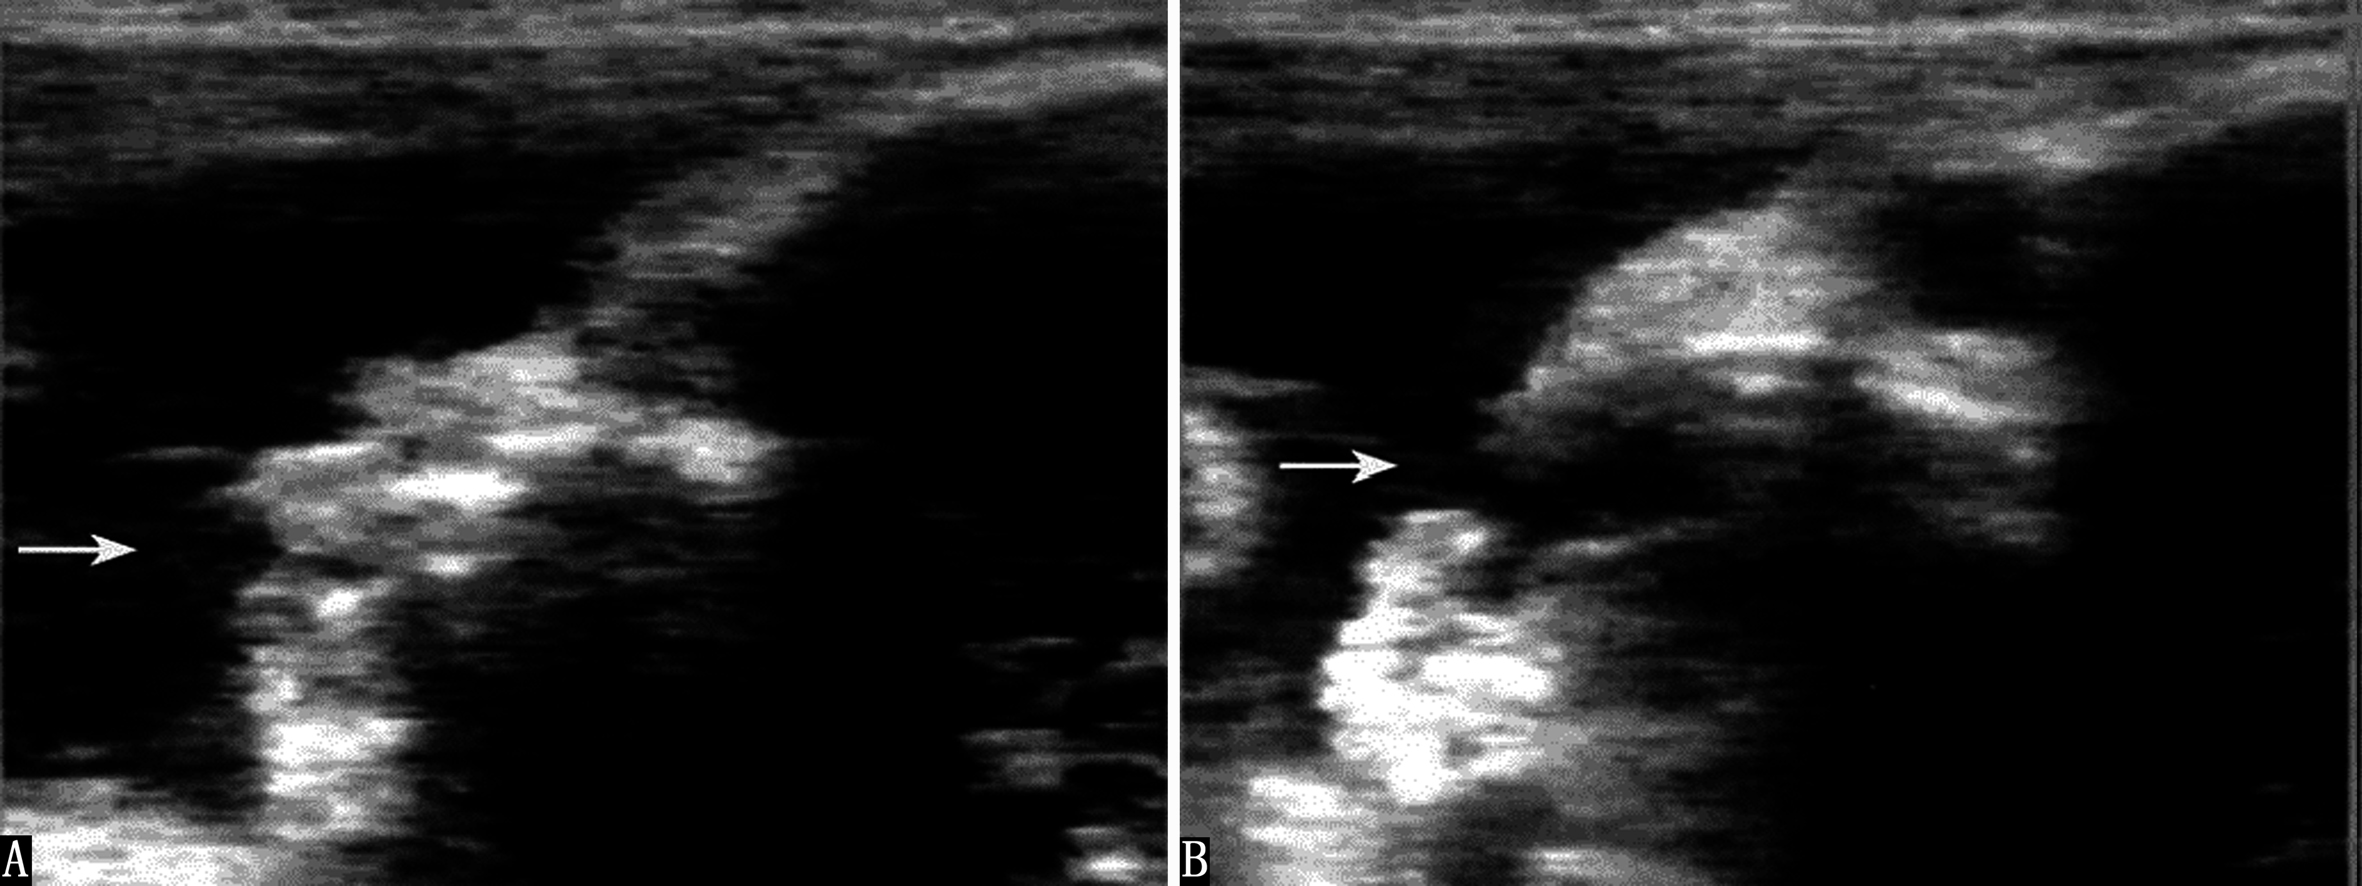

胎儿心脏发生于妊娠后的第18~19天,第21~22天以后心管形成并开始跳动,此时正值停经后的第35~36天,经阴道超声检查即可显示心管活动,经腹超声检查显示的要晚一些。一般在第5周末或第6周、在显示胚胎的同时可显示心管的活动(图1)。二维超声检查显示为快速活动的点状回声,彩色多普勒血流显像检查显示为快速色彩交换的点状回声。

图1早期胎心搏动A:9周胎心搏动(粗箭头,HR168 bpm)和母体活动(细箭头)B:11周胎心血流,HR166BPM